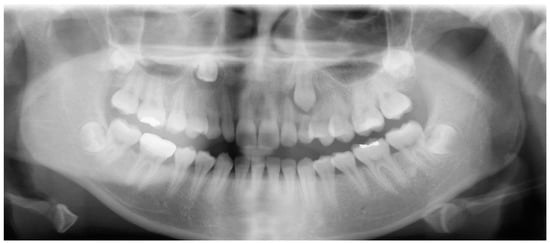

- Evaluation of impacted teeth, a common indication of CBCT in orthodontics. The advantages of CBCT include assessment of the tooth location and position, the stage of development, and status of adjacent teeth. CBCT is justified in these cases, because CBCT has the capability of evaluating the impacted teeth and adjacent structures more accurately than 2D conventional imaging. The benefit–risk ratio is favorable, especially if the CBCT volume is collimated to the impacted tooth. Figure 1, Figure 2, Figure 3 and Figure 4 show an example of impacted maxillary canines, and their proximity to the maxillary lateral incisors. Figure 1 shows an intraoral photograph. The benefit of CBCT acquisition in this case includes the ability to visualize the canines and the lateral incisors in three dimensions, which can be visualized in Figure 2 and Figure 3. In this case, the maxillary right lateral incisor exhibited external root resorption, a finding that would be difficult to see on a conventional 2D panoramic radiograph. Figure 4 shows a Maximum Intensity Projection of a panoramic view derived from the CBCT volume. This unique view is free of magnification, distortion, ghost images, and overlaps frequently seen in conventional 2D panoramic radiography.